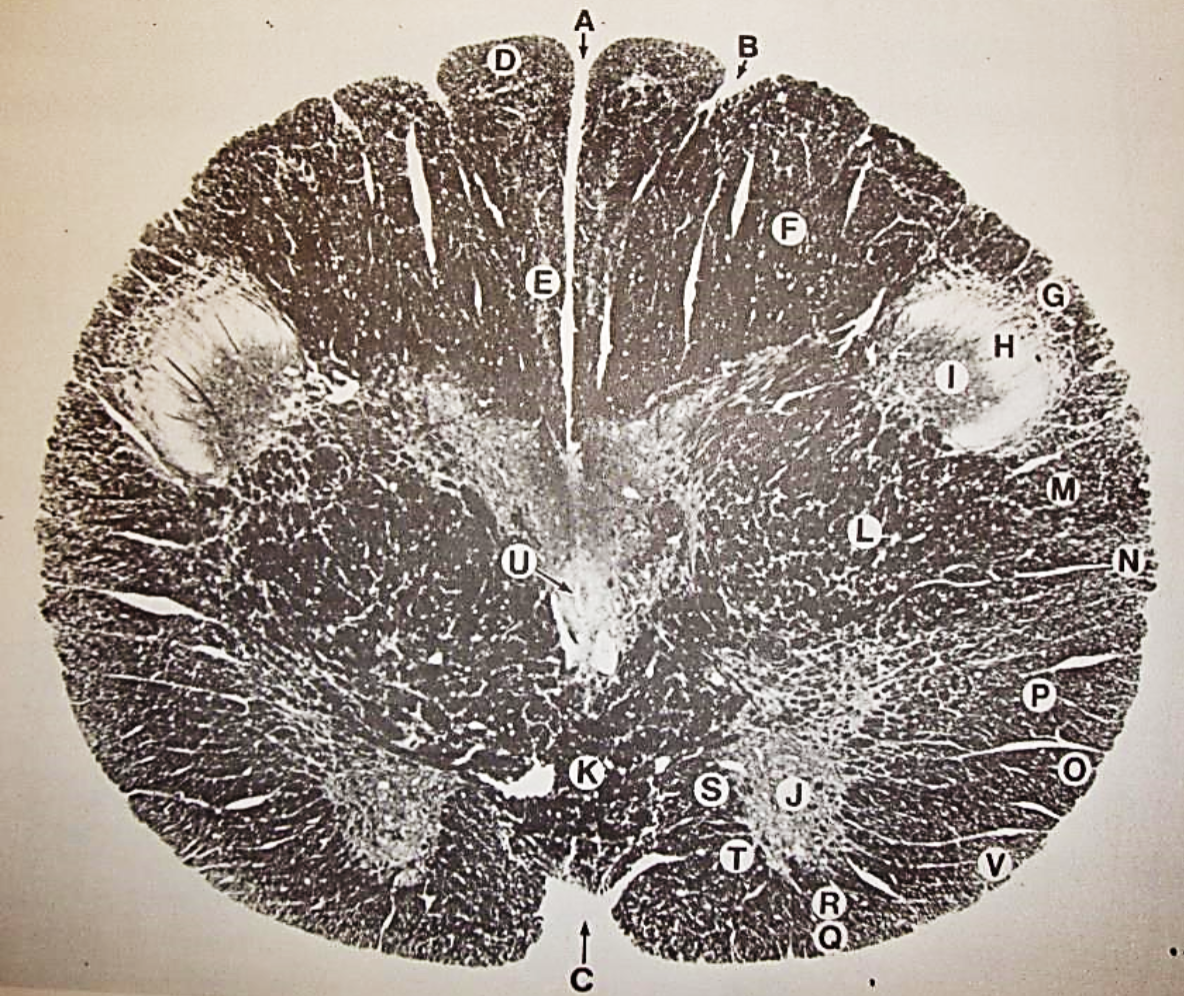

A

Fasciculus gracilis

B

gracile nucleus

C

fasciculus cuneatus

D

cuneate nucleus

E

spinal trigeminal tract

F+G collectively

spinal trigeminal nucleus

H

accessory nucleus

I

pyramidal decussation

J

rubrospinal tract

K

posterior spinocerebellar tract

L

anterior spinocerebellar tract

M

lateral spinothalamic tract

N

anterior spinothalamic tract

O

lateral vestibulospinal tract

P

medial longitudinal fasciculus

Q

tectospinal tract